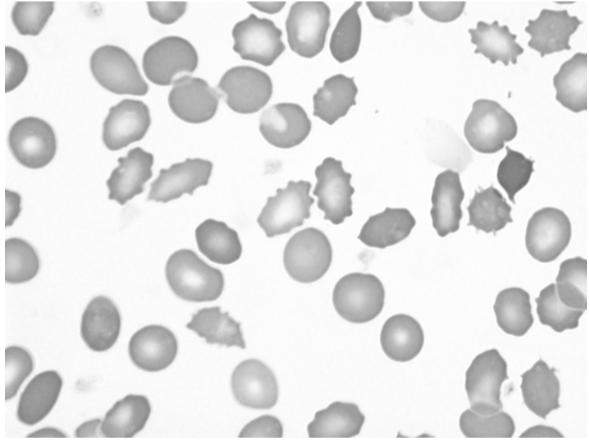

What is this peripheral blood cell classic for?

Acanthocytes and spur cells (abetalipoproteinemia)

Target cells (thalassemia, liver disease)

Echinocytes, including “burr” cells and acanthocytes (uremia)